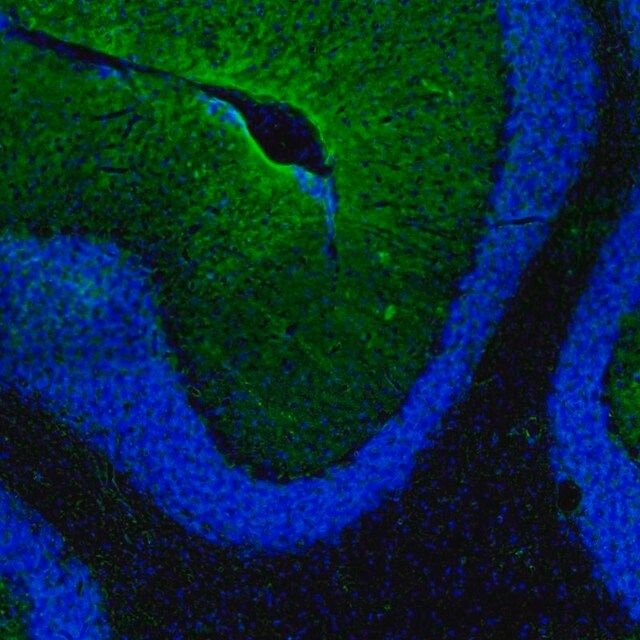

水通道蛋白 4 (aquaporin 4,AQP4) 是一种内源性蛋白,属于水通道蛋白家族,由 13 个成员组成。该基因位于人类 18 号染色体 q11-q12,有 4 个外显子和 3 个内含子。编码的蛋白有 5 个环,由 6 个跨膜结构域干预。环 A、C 和 E 面向浆外区,环 B 和 D 存在于胞浆区。在肺、胃和肾等外周器官中表达。是中枢神经系统表达的主要水通道。它由星形胶质细胞表达,并优先定位于星形胶质细胞的终足突起。它以两种可变剪接形式存在— 长的称为 M1,短的称为 M23。

人类蛋白质图谱项目可细分为三个方面的工作:人类组织图谱、癌症图谱和人类细胞图谱。支持 Tissue and Cancer Atlas 项目而产生的抗体,已经通过免疫组化针对数百个正常和疾病组织进行了测试,通过 Human Cell Atlas 项目最近的努力,很多已经通过免疫荧光法进行了表征,不仅在组织级别,现在也在亚细胞级别绘制了人类蛋白质组图谱。通过点击图像库链接,可以在 Human Protein Atlas (HPA) 位点上查看这些图像和这个庞大数据集的集合。要查看这些协议 和其他有关 Prestige 抗体和 HPA 的有用信息,请访问sigma.com/prestige。

水通道蛋白 4 (aquaporin 4,AQP4) 是脑内主要的水转运体,被认为是维持脑内水分稳态的重要物质。因此,AQP4 可能在脑水肿的发病机制中起重要角色。研究显示,这种转运体在脑缺血中过度表达。因此,它可能有潜力成为缺血性脑水肿的治疗靶点。该基因多态性与脑损伤反应和脑外伤患者的临床预后相关。AQP4 的短亚型 (M23) 有利于颗粒正交排列 (orthogonal array of particles,OAP) 的形成,OAP 的大小由短 (M23):长 (M1) 亚型的比例决定。已知这些 OAP 与视神经脊髓炎 (NMO) 中产生的致病性自身抗体相互作用。因此,对该蛋白的进一步研究可能为 NMO 的发病机制和治疗提供见解。